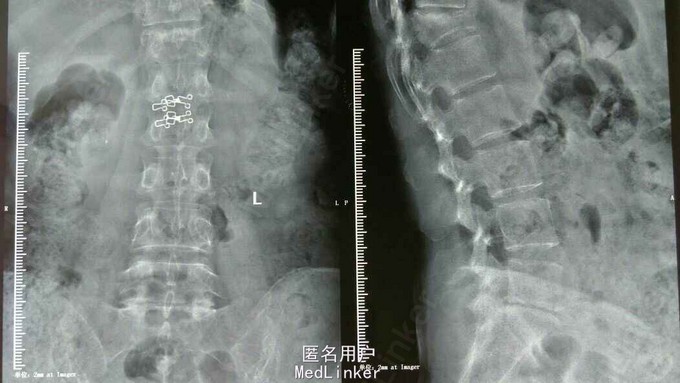

胸椎压缩骨折

患者,女性,55岁,主因外伤致胸背部疼痛3天入院

胸11,12压缩骨折,行胸11,12pkp治疗后,患者腰背部疼痛明显缓解。